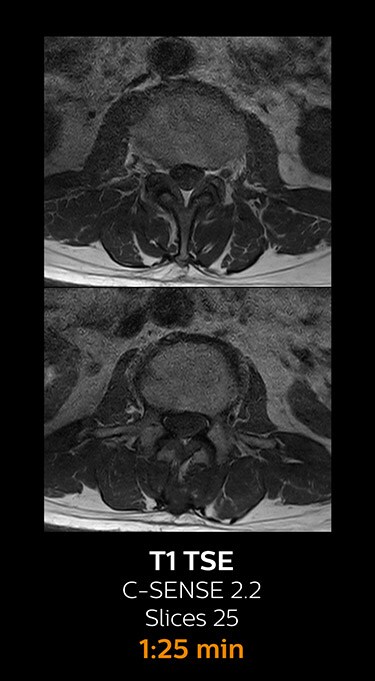

With Compressed SENSE, the scan time for the routine lumbar spine examination at KNC was reduced from 11:41 to 8:17 minutes,

MRI examination of the lumbar spine with Compressed SENSE

Ingenia 3.0T CX

Scan time 8:17 min. (was 11:41 min. without Compressed SENSE)